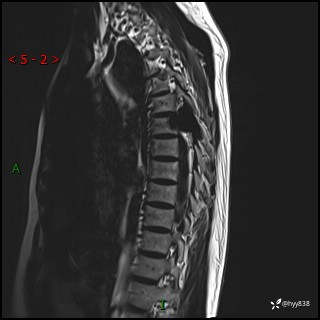

axi T2WI